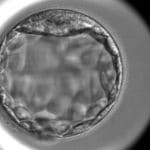

施術経過の一例

症例①

施術前

6BC

施術後

6AA

症例②

6BA

※施術経過の一例です。結果には個人差があります。